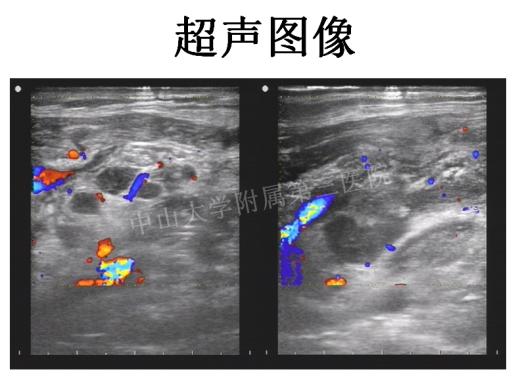

为求进一步诊治,陈女士来到我们医院,普外科、超声科、放射科没有掉以轻心,详细询问病史、详细排查。彩超上出现了疑点:陈女士的脖子上的肿大淋巴结里隐藏了一些小小的钙化和“脓腔”,这难道是淋巴结结核?

几个科的医生又碰到一起,一番商讨后,决定采用微创的超声引导下淋巴结粗针穿刺活检。

超声引导下淋巴结粗针穿刺活检就是在实时超声引导下将穿刺针插入淋巴结中,截取多条淋巴结组织做病理学分析,具有操作时间短、伤口小、精准、安全的优势,可适用于几乎所有浅表淋巴结病变的活检诊断,对于临床治疗决策的制定起到重要作用。